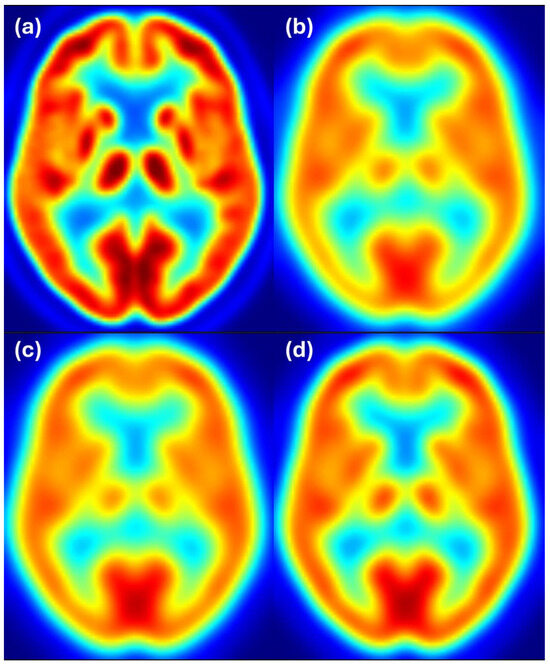

Figure 5 shows axial slices for 6 mm target resolution for Discovery matching HR+ resolution. Here we also see that the Discovery image after filtering with the estimated filter is almost the same as the Discovery image filtered to 6 mm resolution and both images closely resemble the reference image from the HR+ scanner with 6 mm resolution.

Figure 5. Harmonization results for the Discovery scanner matching the HR+ images filtered to 6 mm resolution. Image (a) shows the unfiltered Discovery image, (b) shows the HR+ image at the target resolution of 6 mm, (c) shows the Discovery image after filtering with the estimated filter, and (d) shows the Discovery image filtered to 6 mm resolution. Color scale indicates FDG uptake levels: red for high, green/yellow for medium, and blue for low uptake.